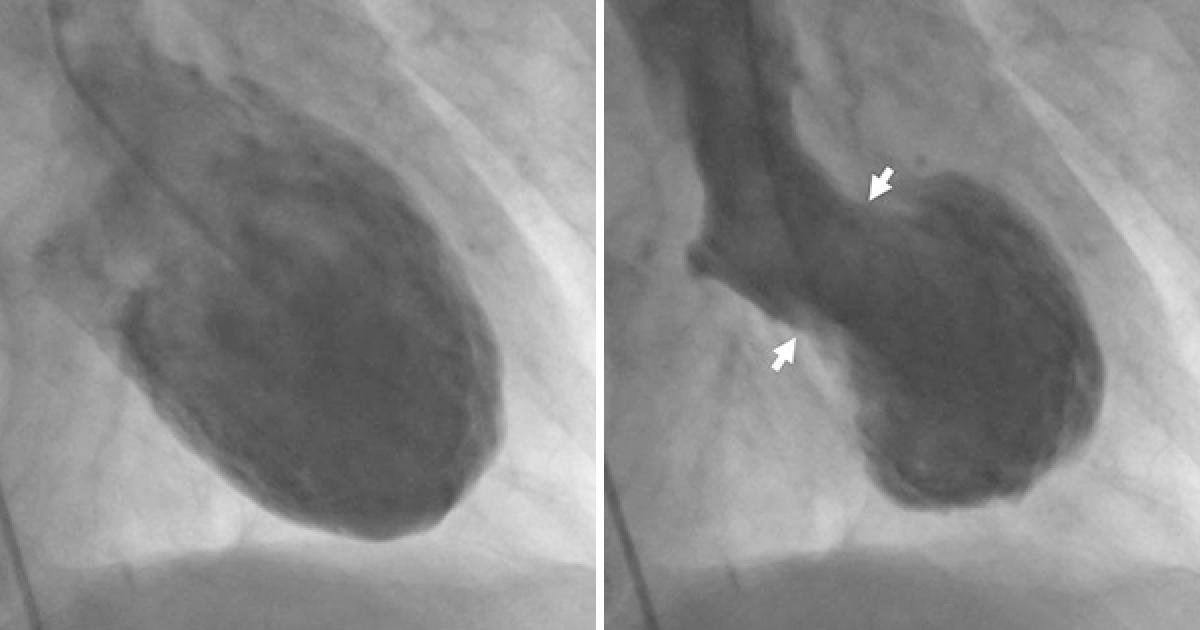

▼心碎症候群是日本在1990年代才確定的病徵,由於患者碰上劇烈的變故時,心臟會突然收縮變形,樣貌很像日本的「章魚壺」(takotsubo),所以也有這個別稱。